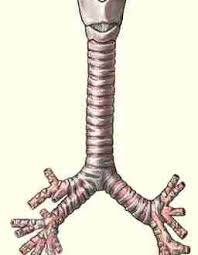

القصبة الهوائية

الرئتين